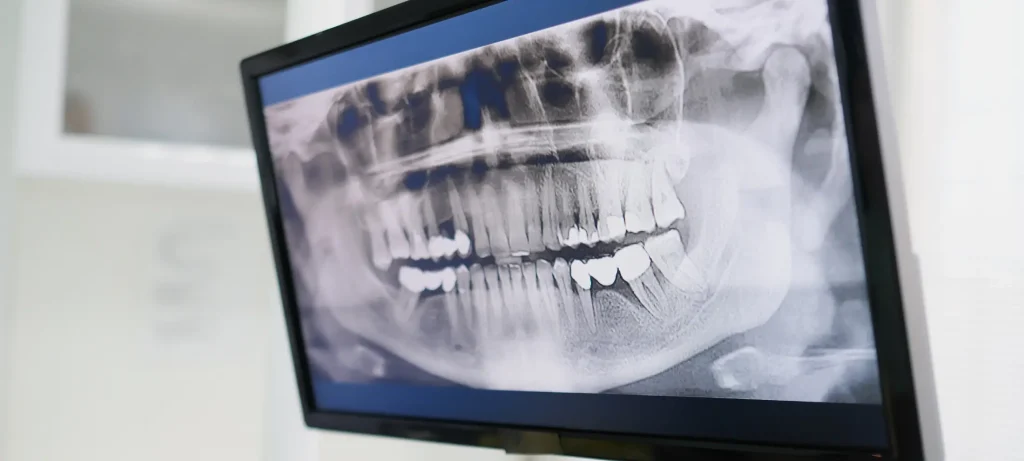

التشخيص عبر الصور الشعاعية والتحليل

تستخدم خوارزميات الذكاء الاصطناعي لتحليل الأشعة السينية وCBCT بدقة عالية للكشف عن التسوس، أمراض اللثة، الآفات الفموية، وحتى الأورام. يساهم هذا الاكتشاف المبكر في تحسين نتائج العلاج وتقليل الإجراءات الجراحية غير الضرورية.

- دقة أعلى وسرعة في التشخيص: يقوم الذكاء الاصطناعي بتحليل الأشعة السينية وCBCT والصور داخل الفم لاكتشاف التسوس، فقدان العظام، الأورام، وحالات أخرى، غالباً بدقة أعلى من العين البشرية.